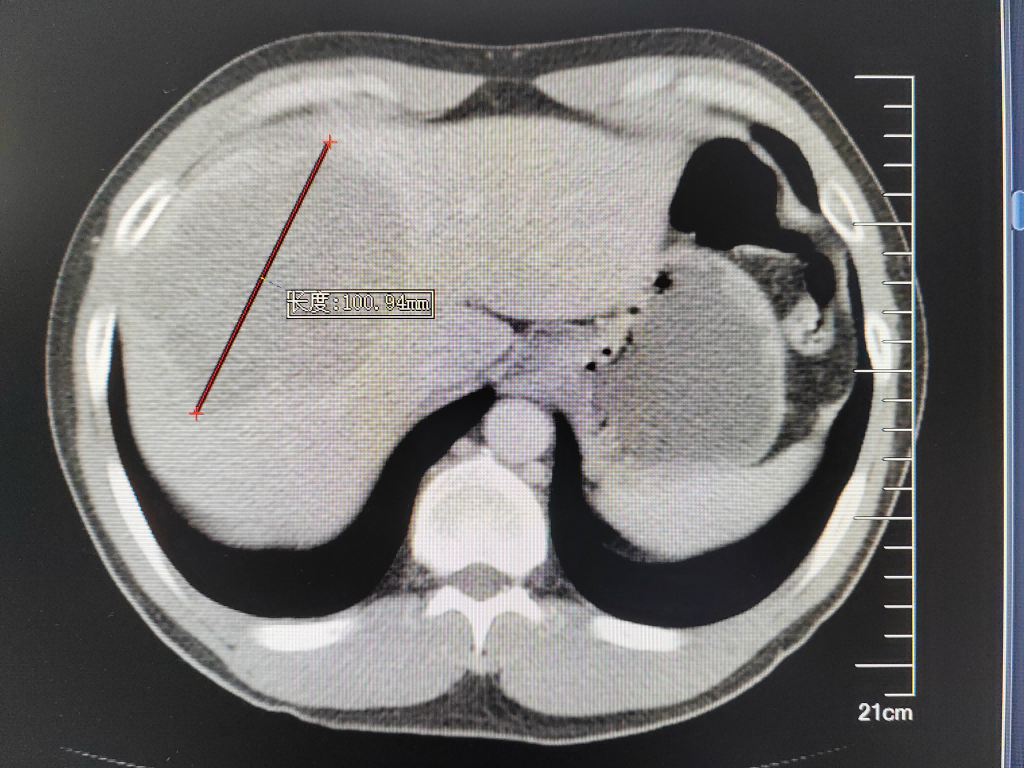

35岁的郑先生,今年3月份出现“右上腹痛”症状,外院行肝胆B超检查提示“肝占位”。患者遂至肿瘤医院肝胆胰外科古松钢副主任医师门诊就诊。入院后查甲胎蛋白为10013.000 ng/mL,腹部增强CT及普美显增强MR检查均显示:肝S4/8肿块,大小约10×8cm,考虑原发性肝癌,伴门脉右支癌栓。

腹部增强CT及MR检查提示肝中叶巨块型肝癌伴门静脉右支癌栓